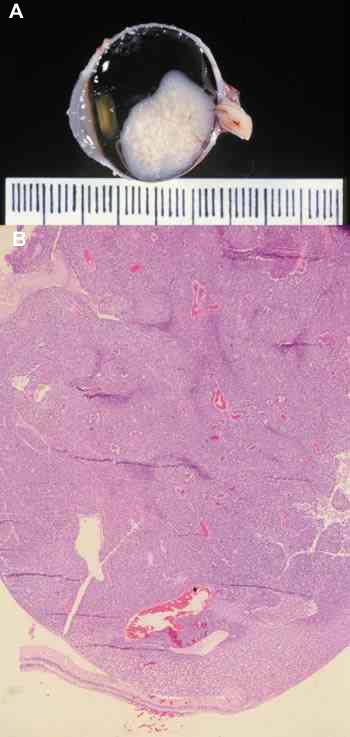

Cinco casos respondieron al tratamiento con predominio de la necrosis, en

algunos existían calcificaciones, pero la fibrosis y otras respuestas

acompañantes eran mínimas. Este tipo de regresión es el que hemos llamado

mínima, en la que existe tumor viable, en mas del 20%. En todos el tumor es

indiferenciado y presenta un marcado índice de proliferación celular con el

Ki-67 (figuras 18 y 19). Dos de los casos (casos 10 y 13), mostraron un

crecimiento masivo, ocupando el tumor la totalidad de la cámara vítrea, y en

ambos casos infiltraban el nervio óptico, pre-laminar en el caso 10 y

post-laminar en el caso 13, en éste último existía infiltración coroidea. En

Figura 18. Retinoblastoma masivo que ocupa la cámara vítrea con

mínima regresión (caso n.º10). H.E. (15x).